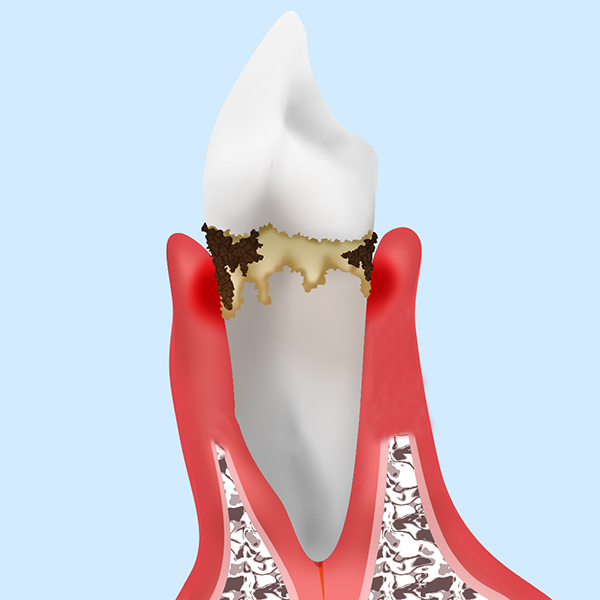

歯周病というのは歯が植わっている土台のアゴの骨を溶かす病気です。

このように歯周病は土台のアゴの骨を溶かしていきます。アゴの骨が溶け続けることにより最終的には歯がグラグラになり抜け落ちていく病気です。

それは、歯周病の原因は歯周病菌です。歯周病菌は人の口の中に必ず住んでいる細菌です。歯周病菌の集合体を歯垢(プラーク)と言います。

この歯垢(プラーク)が長い間、歯の表面に付着していると石灰化して歯石になります。歯石になると硬くこびり付き歯ブラシでは取れない汚れとなります。

歯垢も歯石も歯周病の原因になります。

歯周病菌は、唾液や口の中に入る食事を栄養源として増殖し常時毒素を出します→その毒素によって歯を支えている骨を溶かしていきます。

ここで見ていただきたいのは、健康な方と重度歯周病の方の歯茎の高さはあまり変わらないという所です。要するにパッとお口の中だけを見て歯周病かどうかは分かりません。